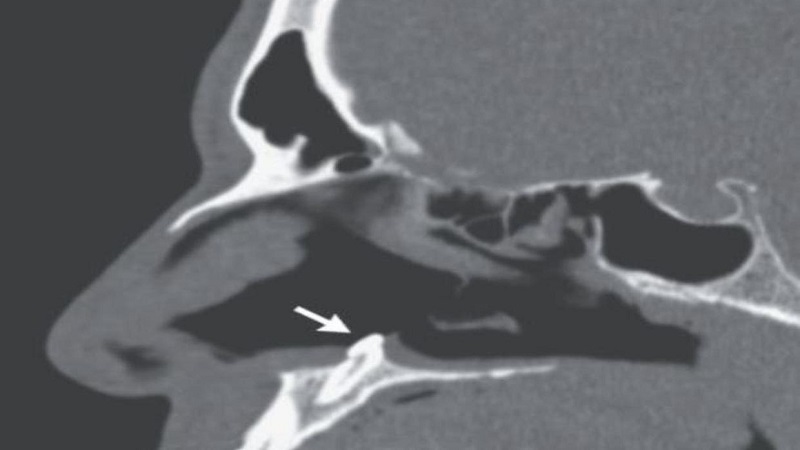

ووفق "روسيا اليوم" فقد وجد طبيب الأنف والأذن والحنجرة الذي فحص الرجل، حاجز منحني متشكل من كتلة بيضاء صلبة في فتحة الأنف وأكد التصوير المقطعي أن هذا الحاجز هو سبب صعوبة التنفس، وتبين أن الحاجز عبارة عن ضرس بطول 14 ملم وعرض 10 ملم.